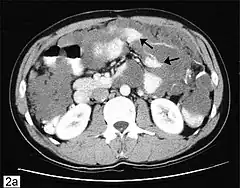

![]() Tomografía axial computarizada de abdomen que muestra la existencia de un pseudomixoma peritoneal con múltiples masas peritoneales señaladas por flechas. | ||